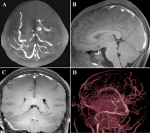

Diagnostic assessment: laboratory testing revealed a markedly elevated serum homocysteine concentration of 114.5 µmol/L (reference range: 6-14 µmol/L). High-resolution 3D-T1W MRI of the brain confirmed extensive cerebral venous thrombosis (Figure 1 A-C) and prominent collateral circulation (Figure 1 D). Collectively, the characteristic triad of ectopia lentis, skeletal fragility, and thrombosis, combined with severe hyperhomocysteinemia, indicates a high probability of homocystinuria. The patient´s neurological condition was identified as extensive cerebral venous thrombosis secondary to hyperhomocysteinemia. However, due to the emergency presentation and critical condition of the patient, a genetic diagnosis for homocystinuria could not be obtained in a timely manner.

Figure 1: brain magnetic resonance imaging of the patient; A-C) maximum intensity projection from 3D-T1W high-resolution magnetic resonance imaging revealed extensive cerebral venous thrombosis in the right sigmoid sinus, transverse sinus, superior sagittal sinus and multiple venous branches on the surface of the cerebrum; D) magnetic resonance venography revealed that the above venous sinuses were not visualized, and plenty of collateral vessels were visible